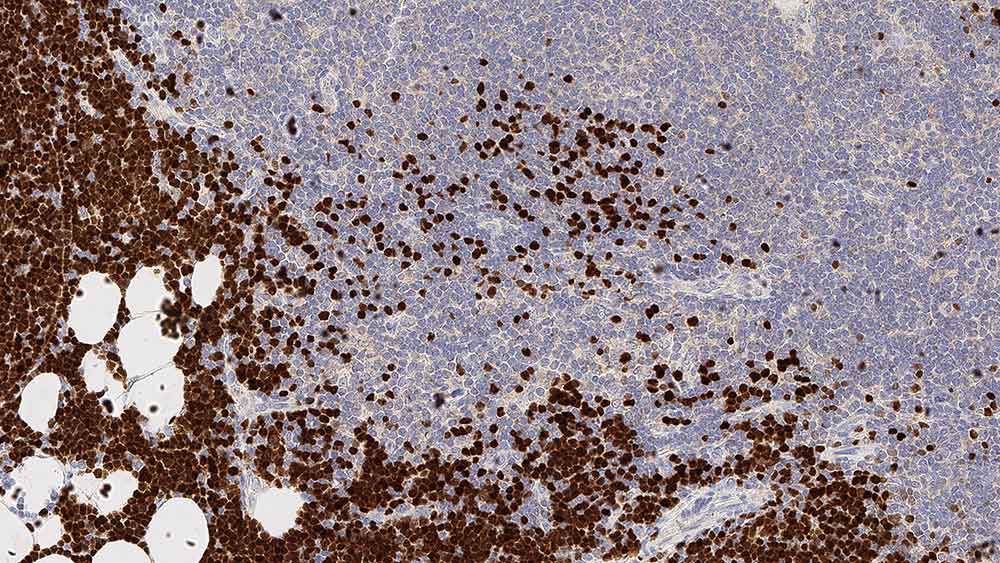

Human thymus: immunohistochemical staining for Terminal Deoxynucleotidyl Transferase. Note nuclear staining for cortical thymic lymphocytes. Terminal deoxynucleotidyl transferase: clone SEN28

Terminal deoxynucleotidyl transferase (TdT) is a DNA polymerase of 58 kD located in the cell nucleus which catalyzes the polymerization of deoxynucleotides at the 3' hydroxyl ends of oligo or polydeoxynucleotide initiators and functions without a template. TdT is reported to be expressed in primitive T and B lymphocytes of the normal thymus and bone marrow. The identification of TdT-positive cell populations in primary and secondary lymphoid organs during maturation of the immune system is one area of interest but it is the reported occurrence of high levels of enzyme activity in white blood cells and bone marrow in certain leukemias which is of particular interest.